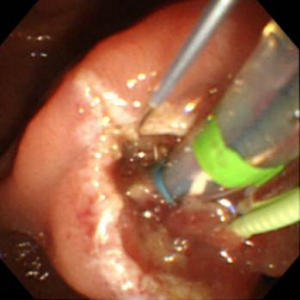

結石が胆管を閉塞し、胆管炎、閉塞性黄疸、急性膵炎などを発症します。緊急の処置が必要な場合が多く、放置すると命に係わる場合があります。通常バスケットカテーテルを用いて、結石を取り除きますが、石が大きい場合はESWL(体外衝撃波結石破砕術)を併用し排石する場合もあります。

ESWLとEST後large balloonによる乳頭拡張術を併用し完全排石に成功した巨大総胆管結石の一例